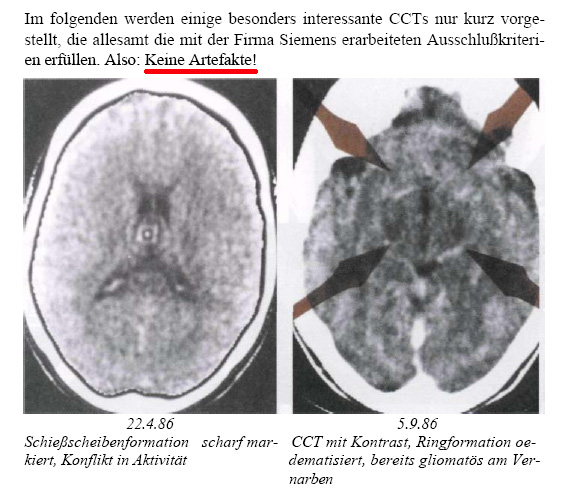

Hamer believes that a sudden shock-like onset of an unforeseen so-called biological conflict leads to a so-called "Dirk-Hamer-Syndrome" (DHS) which immediately (within a fraction of a second) produces a "cancer" in an organ. He postulates that every DHS-related process will take place synchronously in the brain, in the "organic brain" and in the organ. He adds that tumours forming were allegedly controlled by that part of the brain ontogenetically connected with the organ in question. Hamer calls this the "ontogenetic system of tumours". In the brain, the biological conflict is said to give rise to the development of a so-called "Hamer-focus". By this, Hamer means structures seen in CT brain scans which are shaped like a shooting target, or a single, mathematically precise circle. He claims the locations of these Hamer-foci and their degree of severity were correlated to the organs affected, the underlying biological conflict and the phase of the conflict. The non-radiologist Hamer adds that radiology was not able to detect these Hamer-foci until his inventions in 1981. According to New Medicine, the patient's right- or left-handedness was also significant.

Artefacts were quite frequent at the beginning of computer tomography, and a particular type of artefact, the ring artefact[1] was sometimes seen in early CT scanners, especially those of third generation, and are very seldom today due to progress in scanner technology. These artefacts are machinery-caused shapes superimposing the underlying scan. Usually they are easy to recognize and can be avoided by complying with the indications given by the manufacturer. Ring artefacts are always precise and perfect dark and bright concentric circles. Sometimes they may appear only as segments of a perfect ring and sometimes only one single circle may appear (if a specific single sensor is defective or not calibrated). The centre of the concentric circles corresponds with the axis of rotation of the scanner and sometimes may be seen outside of the subject or object in the scanner. These circles are caused by a defective sensor, a sensor with different sensibility than the other sensors, or after having forgotten to calibrate the entire scanner. An old fashioned CT-scanner had to be calibrated (with air or a water-phantom) at the beginning of service. After some hours a message told the operator to stop scanning and to perform a new calibration procedure as temperature influences and other effects were slowly modifying the performance of the individual sensors. These sensors must work at the limit of sensibility to avoid too large doses of radiation for the patient. Knowing this, an expert CT-operator may also be able to produce artificial rings-artefacts on purpose by avoiding calibration or by manipulating the device.

Hamer and his followers often name a certificate of a German CT-manufacturer, the Siemens company, dated December 22nd, 1989. They believe that this paper excluded the hypothesis that the Hamer-focus in fact was a technical artefact, namely a ring artefact. But the opposite is true. This document can be used to identify ring artefacts in many brain scans shown by Hamer. This documents does not deal with New Medicine or Hamer-foci.

It was Hamer himself to request this document (!) in 1989 that was written on December 22nd.[2] Hamer was one of the two persons signing the letter, the other was a Siemens engineer (not a radiologist). Hamer at that time had already been barred as a physician for three years and had to face the reproval by radiologists and other physicians to show artefacts. This document tells from the point of view of Siemens several conditions that are not compatible with ring artefacts.

Translation: Erlangen, 22.12.89. Possible ring artefacts. The undersigned [Hamer and engineer Feindor] have developed 8 [in fact only 7] excluding criteria regarding the presence of ring artefacts. Ring artefact do not appear if

This Siemens document does not mention New Medicine or Hamer and does not exclude the fact that Hamer shows ring artefacts in his books. The precise circular shape of many structures showed by Hamer correspond to item 2 in this document. There are no neuropathological reports that any of the Hamer-foci have ever been identified to be of glial-tissue according to item 3.

CT brain scans presented by R. G. Hamer

The pictures are from his book: [10].